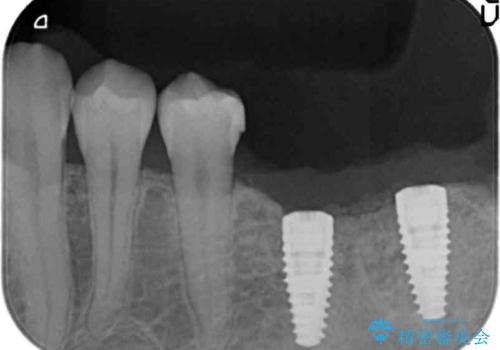

CT画像より骨の量は少なくそのままではインプラントの埋入が難しい状態です。

骨造成を行い安定したインプラントの環境を整える治療を計画します。

- 80万円(インプラント×2・骨造成・アバットメント×2)・ジルコニアクラウン×2)費用は治療当時の料金となります